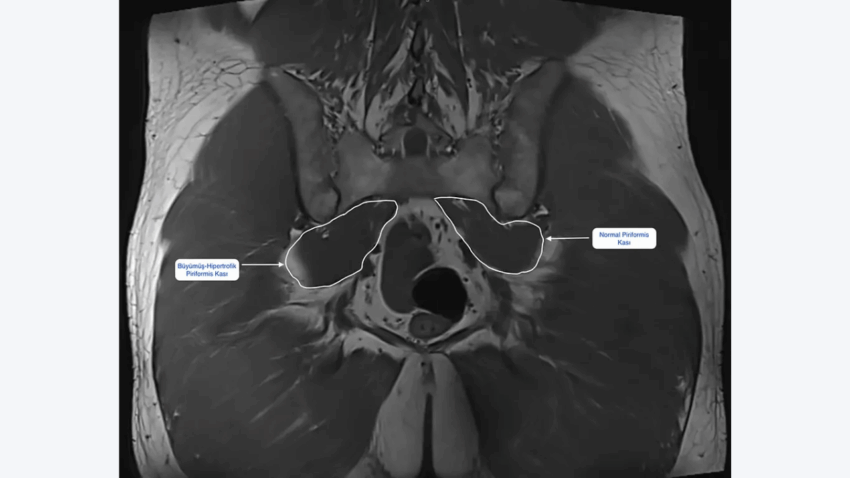

- Görüntüleme: Önce çoğunlukla bel MR’ı istenir; bel fıtığı, kanal darlığı gibi sorunlar dışlanmaya çalışılır. Gerekirse pelvis MR ile piriformis kasının kalınlığı, çevre dokularla ilişkisi ve olası ödem alanları değerlendirilir.

- MR veya benzeri görüntülemelerde piriformis kasında bariz kalınlaşma, ödem veya anormal ilişki saptanması